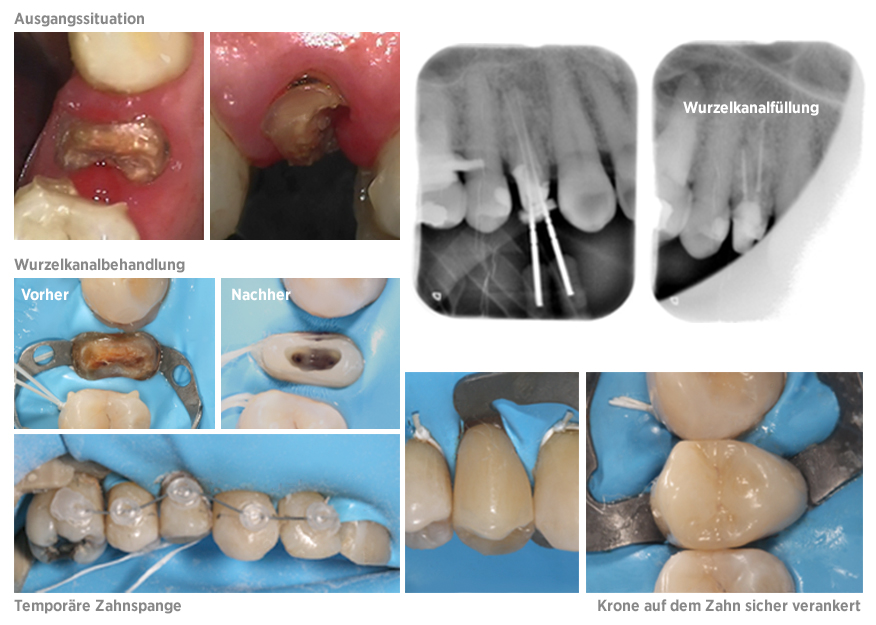

Fall der Woche 16.03.2017

Wieder ein interessanter Fall in unserer Praxis. Ein Patient stellte sich bei uns mit einem tief zerstörten Zahn und einer Entzündung an der Wurzelspitze im Oberkiefer vor.

Nun stellt sich die Frage: Können wir den Zahn erhalten oder müssen wir ihn extrahieren? Getreu dem Motto "nichts ist so gut wie der eigene Zahn" begannen wir mit der Therapie. Die Patientin bekam eine Wurzelkanalbehandlung, sowie einen Glasfaserstift, um den anschließenden Aufbau zu fixieren. Danach wurde der Zahn langsam Stück für Stück mit einer temporären festen Zahnspange aus dem Kiefer heraus gezogen, damit wir eine Krone sicher auf dem Zahn verankern können.

Der Zahn ist seit dem Beschwerdefrei und wird in regelmäßigen Abständen kontrolliert.